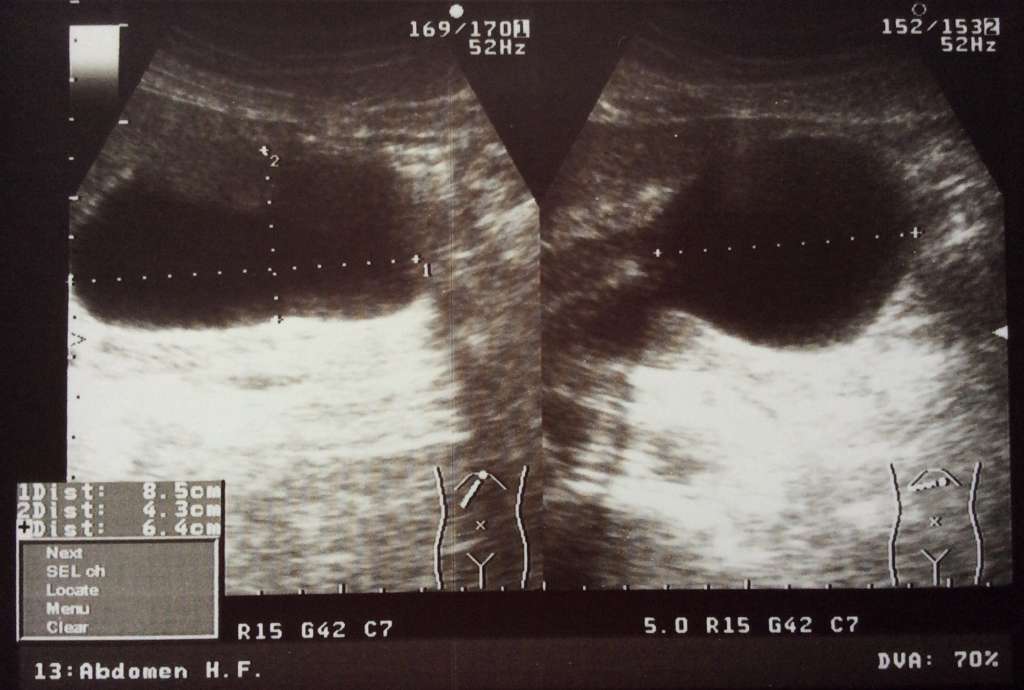

УЗИ абсцесс брюшной полости